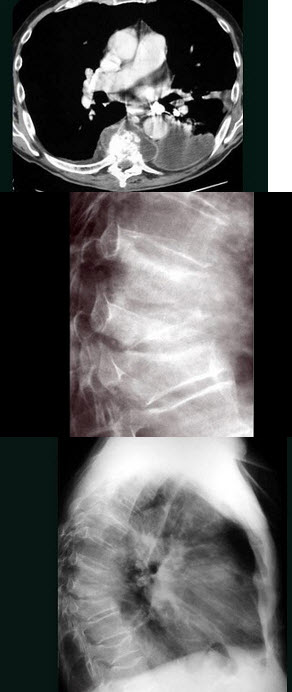

D.关节骨质增生

男,71岁,背部酸痛,低热,乏力,消瘦2月余,结合影像学表现,最可能的诊断是()

A.脊柱转移瘤

B.化脓性脊柱炎

C.脊椎结核

D.椎体压缩骨折

E.阻滞椎